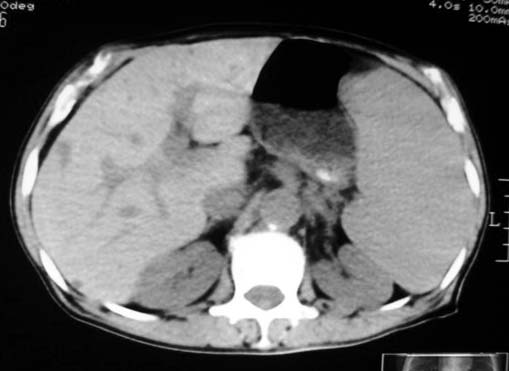

以下是引用dyqct在2007-4-20 16:38:00的发言:[br]考虑:1、巨脾;[br] 2、肝内多发低密度,首先考虑转移瘤;[br] 3、胆囊多发结石。

以下是引用andymaomao在2007-4-20 16:47:00的发言:[br]肝脾增大,肝内胆管扩张,且可见多发小囊性低密度灶,胆囊窝区高密度影,手术化疗病史,贫血....[br]1.肝脾大及贫血与术后化、药疗有关;[br]2.胆囊窝区高密度影,术后改变?肝内胆管扩张,积液?[br]3.肝内多发低密度灶,性质?建交增强